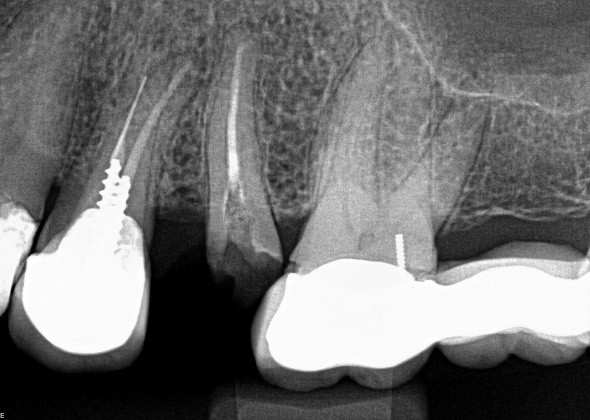

13. (Select ONE OR MORE correct answers)

Which of the following describe(s) the endodontic treatment of tooth 4.6?